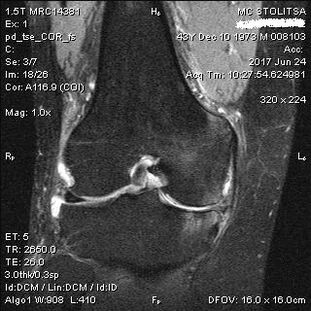

The diagnosis of arthrosis of the knee joint takes place in the office of a rheumatologist or orthopedist.The doctor examines the affected joint, palpates it, listens to complaints and asks additional questions.Performs several tests - for example, whether the patient wants to bend his leg or walk a few steps.Then, if it is necessary to clarify the stage of the disease or the nature of pathological changes, he will refer you for additional studies.For example, for computed tomography or radiography.